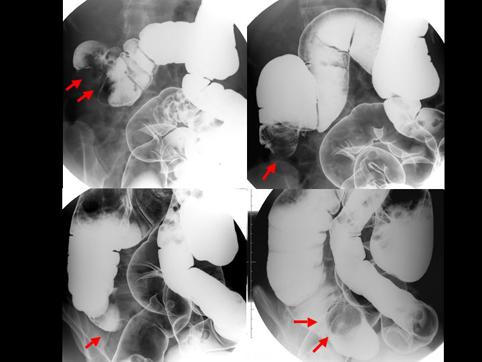

질환(병리주체)의 분류 악성 림프계종양/악성 림프종

부위(장기별) 소장/회장

검사방법 X-P

종양의 육안분류 1형(종괴형)/

종양의 최대경(밀리미터) 35~40